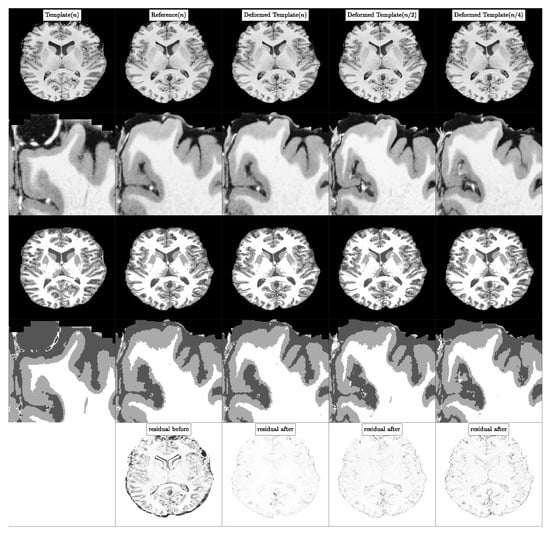

5.4. Experiment 2B: High Resolution Real Data Registration

5.4.1. Datasets

5.4.2. Procedure

- Upsample the respective NIREP image from to using linear interpolation.

- Register MRI250 to the upsampled NIREP image using CLAIRE and transport (which corresponds to the MRI250 image) using the resulting velocity v and solving Equation (3) to obtain the deformed template image . We set the tolerance for the relative gradient norm to . We lower the tolerance compared to other runs to obtain a potentially more accurate registration result. We use the default regularization parameters and . Consequently, we do not perform a parameter search to estimate an optimal regularization parameter for this registration. We want to keep the downstream registration performance analysis, where we will use parameter search, oblivious to the process of generating the high-resolution reference image.

5.4.3. Results

5.4.4. Observations